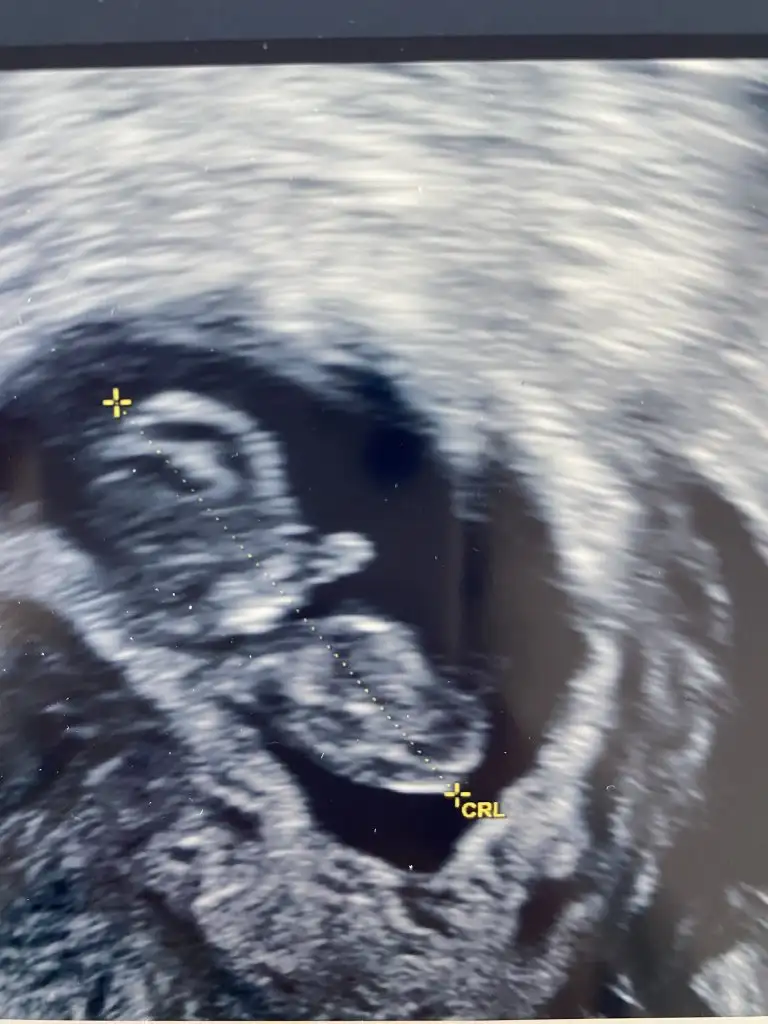

Merhaba ne güzel maşallah her gittiğinizde bebiş sizi şaşırtmışKızlar merhaba bende sizle aynıyım ama kayıt olmadım sayfaya. Sizde bebek önde çıkıyor diyince bende anlatmak istedim. Ben ilk kese ve kalp atışını girmek için 6+4 olması gerekiyordu son adet tarihinden eminim ben yazarım hep çünkü ama gidince 7+3 çıktı. Daha sonra 7+3ten hesaplayarak 3 hafta sonra gittim bu seferde 10+3 çıkması gerekirken 11+3 çıktıbakalım ne çıkacak bidahaki ay cinsiyeti merak etmiyordum ama benimle beraber kalanların çoğu erkek öğrendi burasıda öyle resmen şaşırtıcı

Canm biz 4 gün önden gidiyoruz ama yuzde 90 kız dedi doktorumCanım önde giderse erkek miymiş ?benimde önden gidiyormuş hatta boyu mm olarak haftasına göre uzun dedi doktor . Bakalım tutacak mı bu teoriler

bence erkek ama çok anlamamKızlarrr varmı acaba anlayan fikri olan cinsiyet tahmini alalımmm![]()